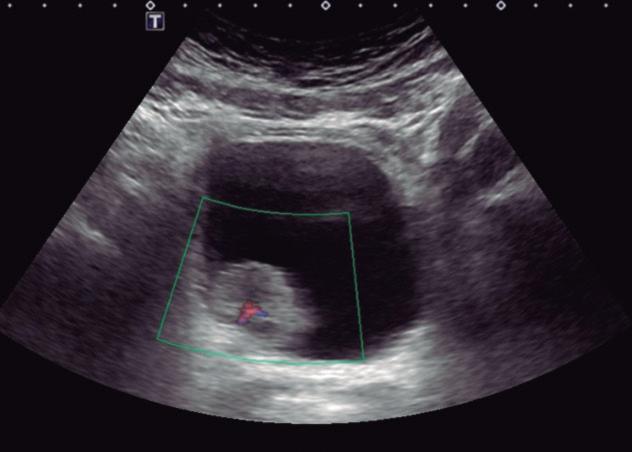

Fig. 2-18. Nódulo na bexiga com vascularização ao Doppler.